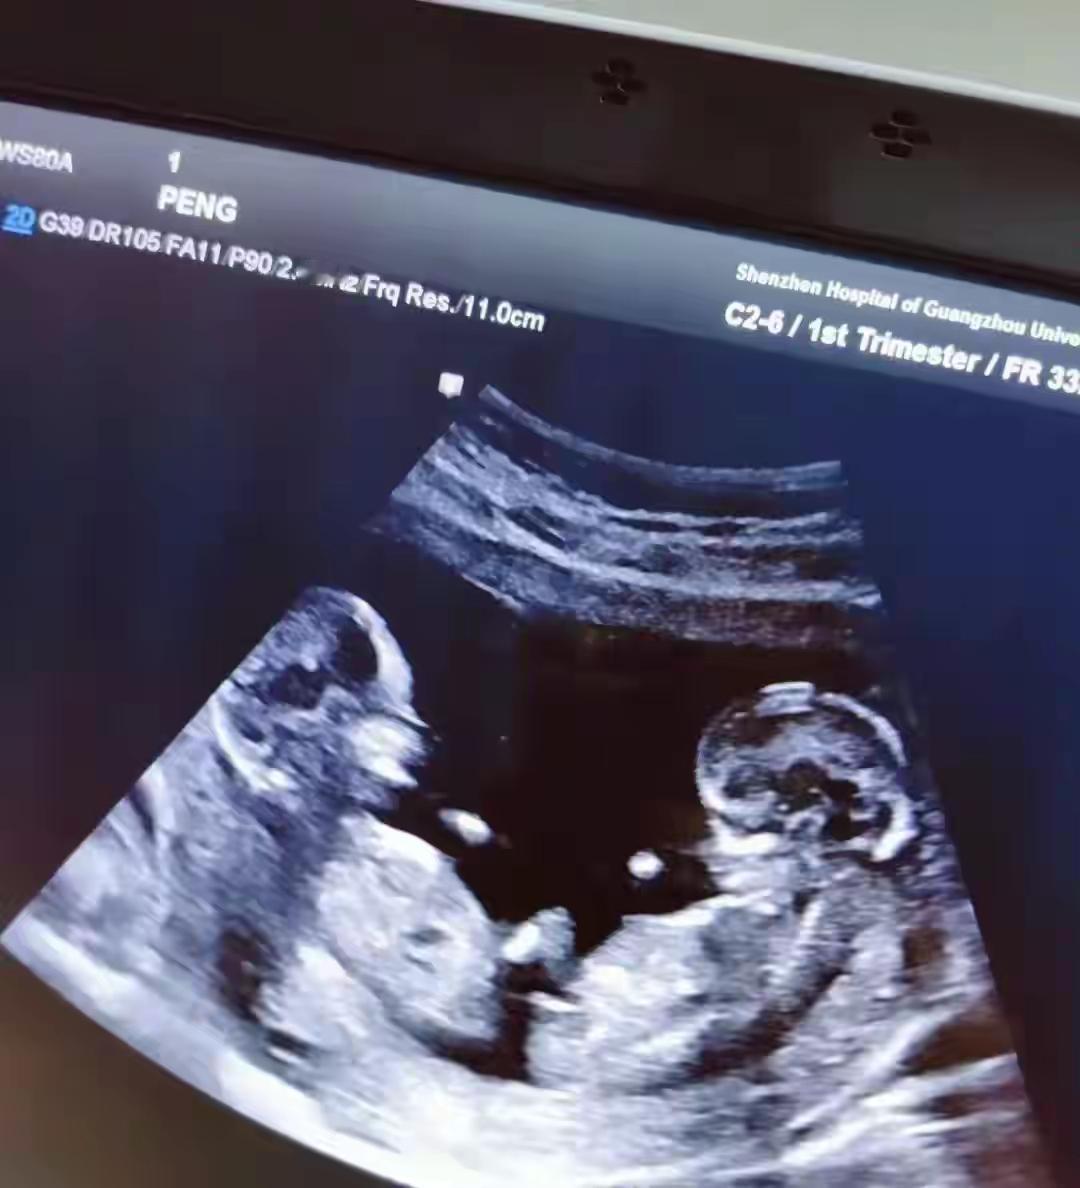

三次产检都没查出双胞胎,真的只是孩子贴太紧? 有人说这就是个意外,俩娃贴太近B超看不出来太正常了,可我就想抬个杠,真就全怪孩子位置?怀孕八个多月,三次产检啊,就算娃贴得紧,专业的检查就一点端倪都看不出来? 说娃贴太紧被挡住的,我知道B超不是万能的,偶尔有位置特殊看不清楚的情况,但这都孕晚期了,胎儿都那么大了,三次检查愣是一次都没发现,这能全赖孩子?要是说孕早期孕囊小没看出来还能理解,八个多月啊,就算一个挡着一个,胎心、胎位、肚子的大小,这些难道就一点异常都没有?医生就一点没察觉不对劲?